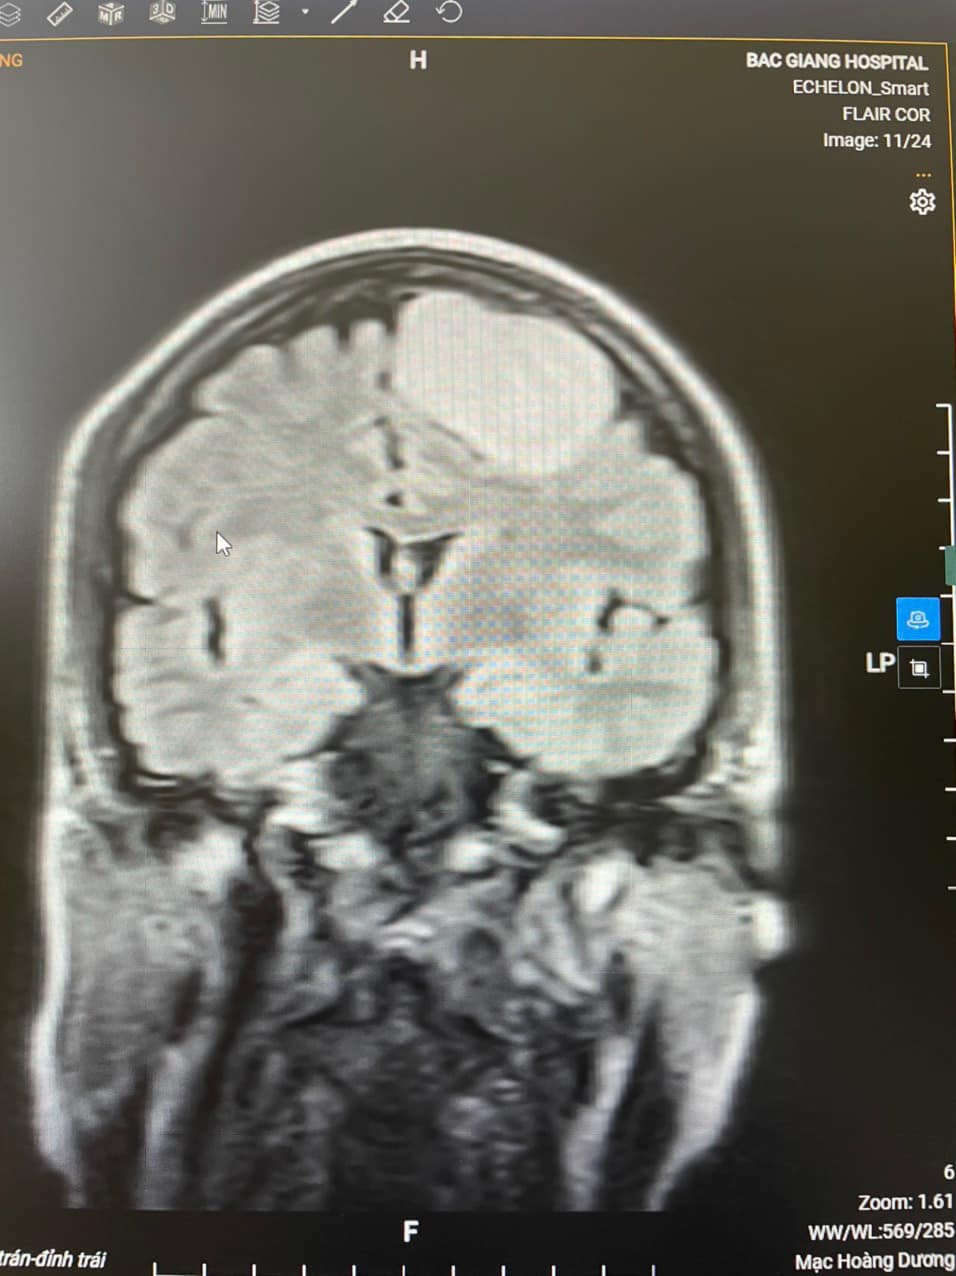

Sau khi vào khoa Ngoại thần kinh của Bệnh viện Đa khoa tỉnh, bác sĩ đã tiến hành khám và chỉ định chụp cộng hưởng từ có tiêm thuốc cản quang để tìm nguyên nhân thì thấy một khối u có kích thước 36x48x54mm vùng trán đỉnh trái của người bệnh. Bệnh nhân được chẩn đoán là u não vùng trán đỉnh trái. Các bác sĩ của Bệnh viện Đa khoa tỉnh đã tiến hành hội chẩn với chuyên gia đầu ngành thần kinh sọ não của Bệnh viện Hữu Nghị Việt Đức và sau đó đi tới quyết định phẫu thuật lấy khối u trên. Trước đây, tại Bệnh viện Đa khoa tỉnh đã thực hiện nhiều ca mổ u não, u màng não nhưng chưa từng thực hiện ca phẫu thuật lấy u não nào có kích thước lớn lại gần trung khu vận động như vậy nên người nhà người bệnh còn thấy phân vân. Tuy nhiên, sau khi được nghe các bác sĩ giải thích, tư vấn, người nhà bệnh nhân đã hoàn toàn tin tưởng và đồng ý thực hiện phẫu thuật. Ca phẫu thuật kéo dài hơn 4h đồng hồ, kíp mổ gồm BS.CKII Mạc Hoàng Dương, Trưởng khoa Ngoại thần kinh; BS Nguyễn Minh Hải, khoa Phẫu thuật Gây mê hồi sức cùng các cộng sự; dưới sự giúp đỡ của chuyên gia TS.BS Bùi Huy Mạnh, Khoa Phẫu Thuật Thần kinh I, Bệnh việt Hữu Nghị Việt Đức. Với ê-kíp phẫu thuật có kinh nghiệm chuyên môn sâu cùng các trang thiết bị hiện đại, khối u lớn trong não đã được lấy ra trọn vẹn.